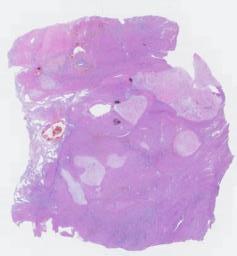

临床资料: 女,56岁。送检部位:全切子宫。病史:月经紊乱6年,阴道出血5月余。彩超:子宫体积125×90x99mm,子宫底前壁见93x59mm低回声,边界不清,回声不均匀,腺肌症合并腺肌瘤?

大体所见: 破碎子宫,总体积11.0×7.0x5.0cm,肌壁厚3.0cm,切面局部呈暗红色,内膜灰红色,见一息肉样隆起,大小1.5×0.9×0.4cm。另见灰白组织数块,总体积10.0x7.0x5.0cm,切面灰白灰黄色,部分质软,粘液胶冻状。